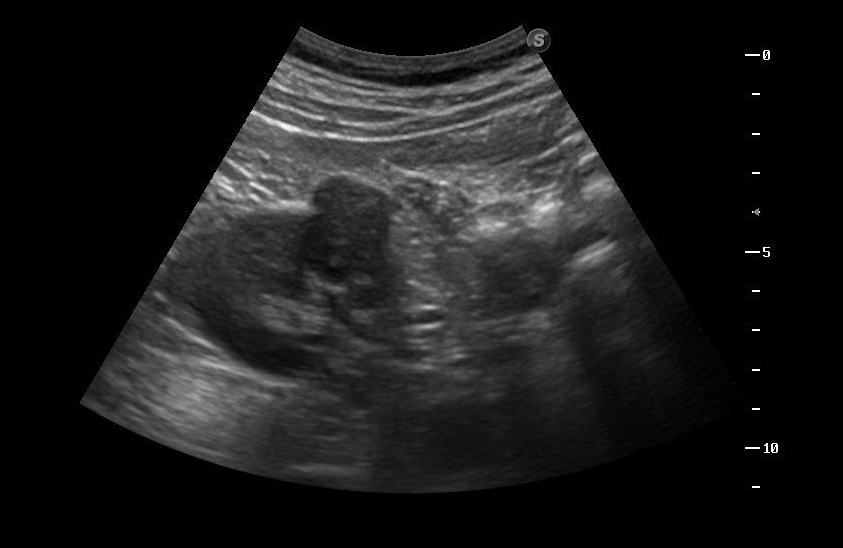

гипоэхогенное образование в среднем сегменте, деформирующее контур почки...наверное рак

Что-то на узи на кисту не похоже...

В том то и дело. Но тем не менее - это киста, анамнез уже несколько лет.besliu писал(а):Что-то на узи на кисту не похоже...

Динамики нет, на последнем видео четко видна киста при включенной 2й гармонике